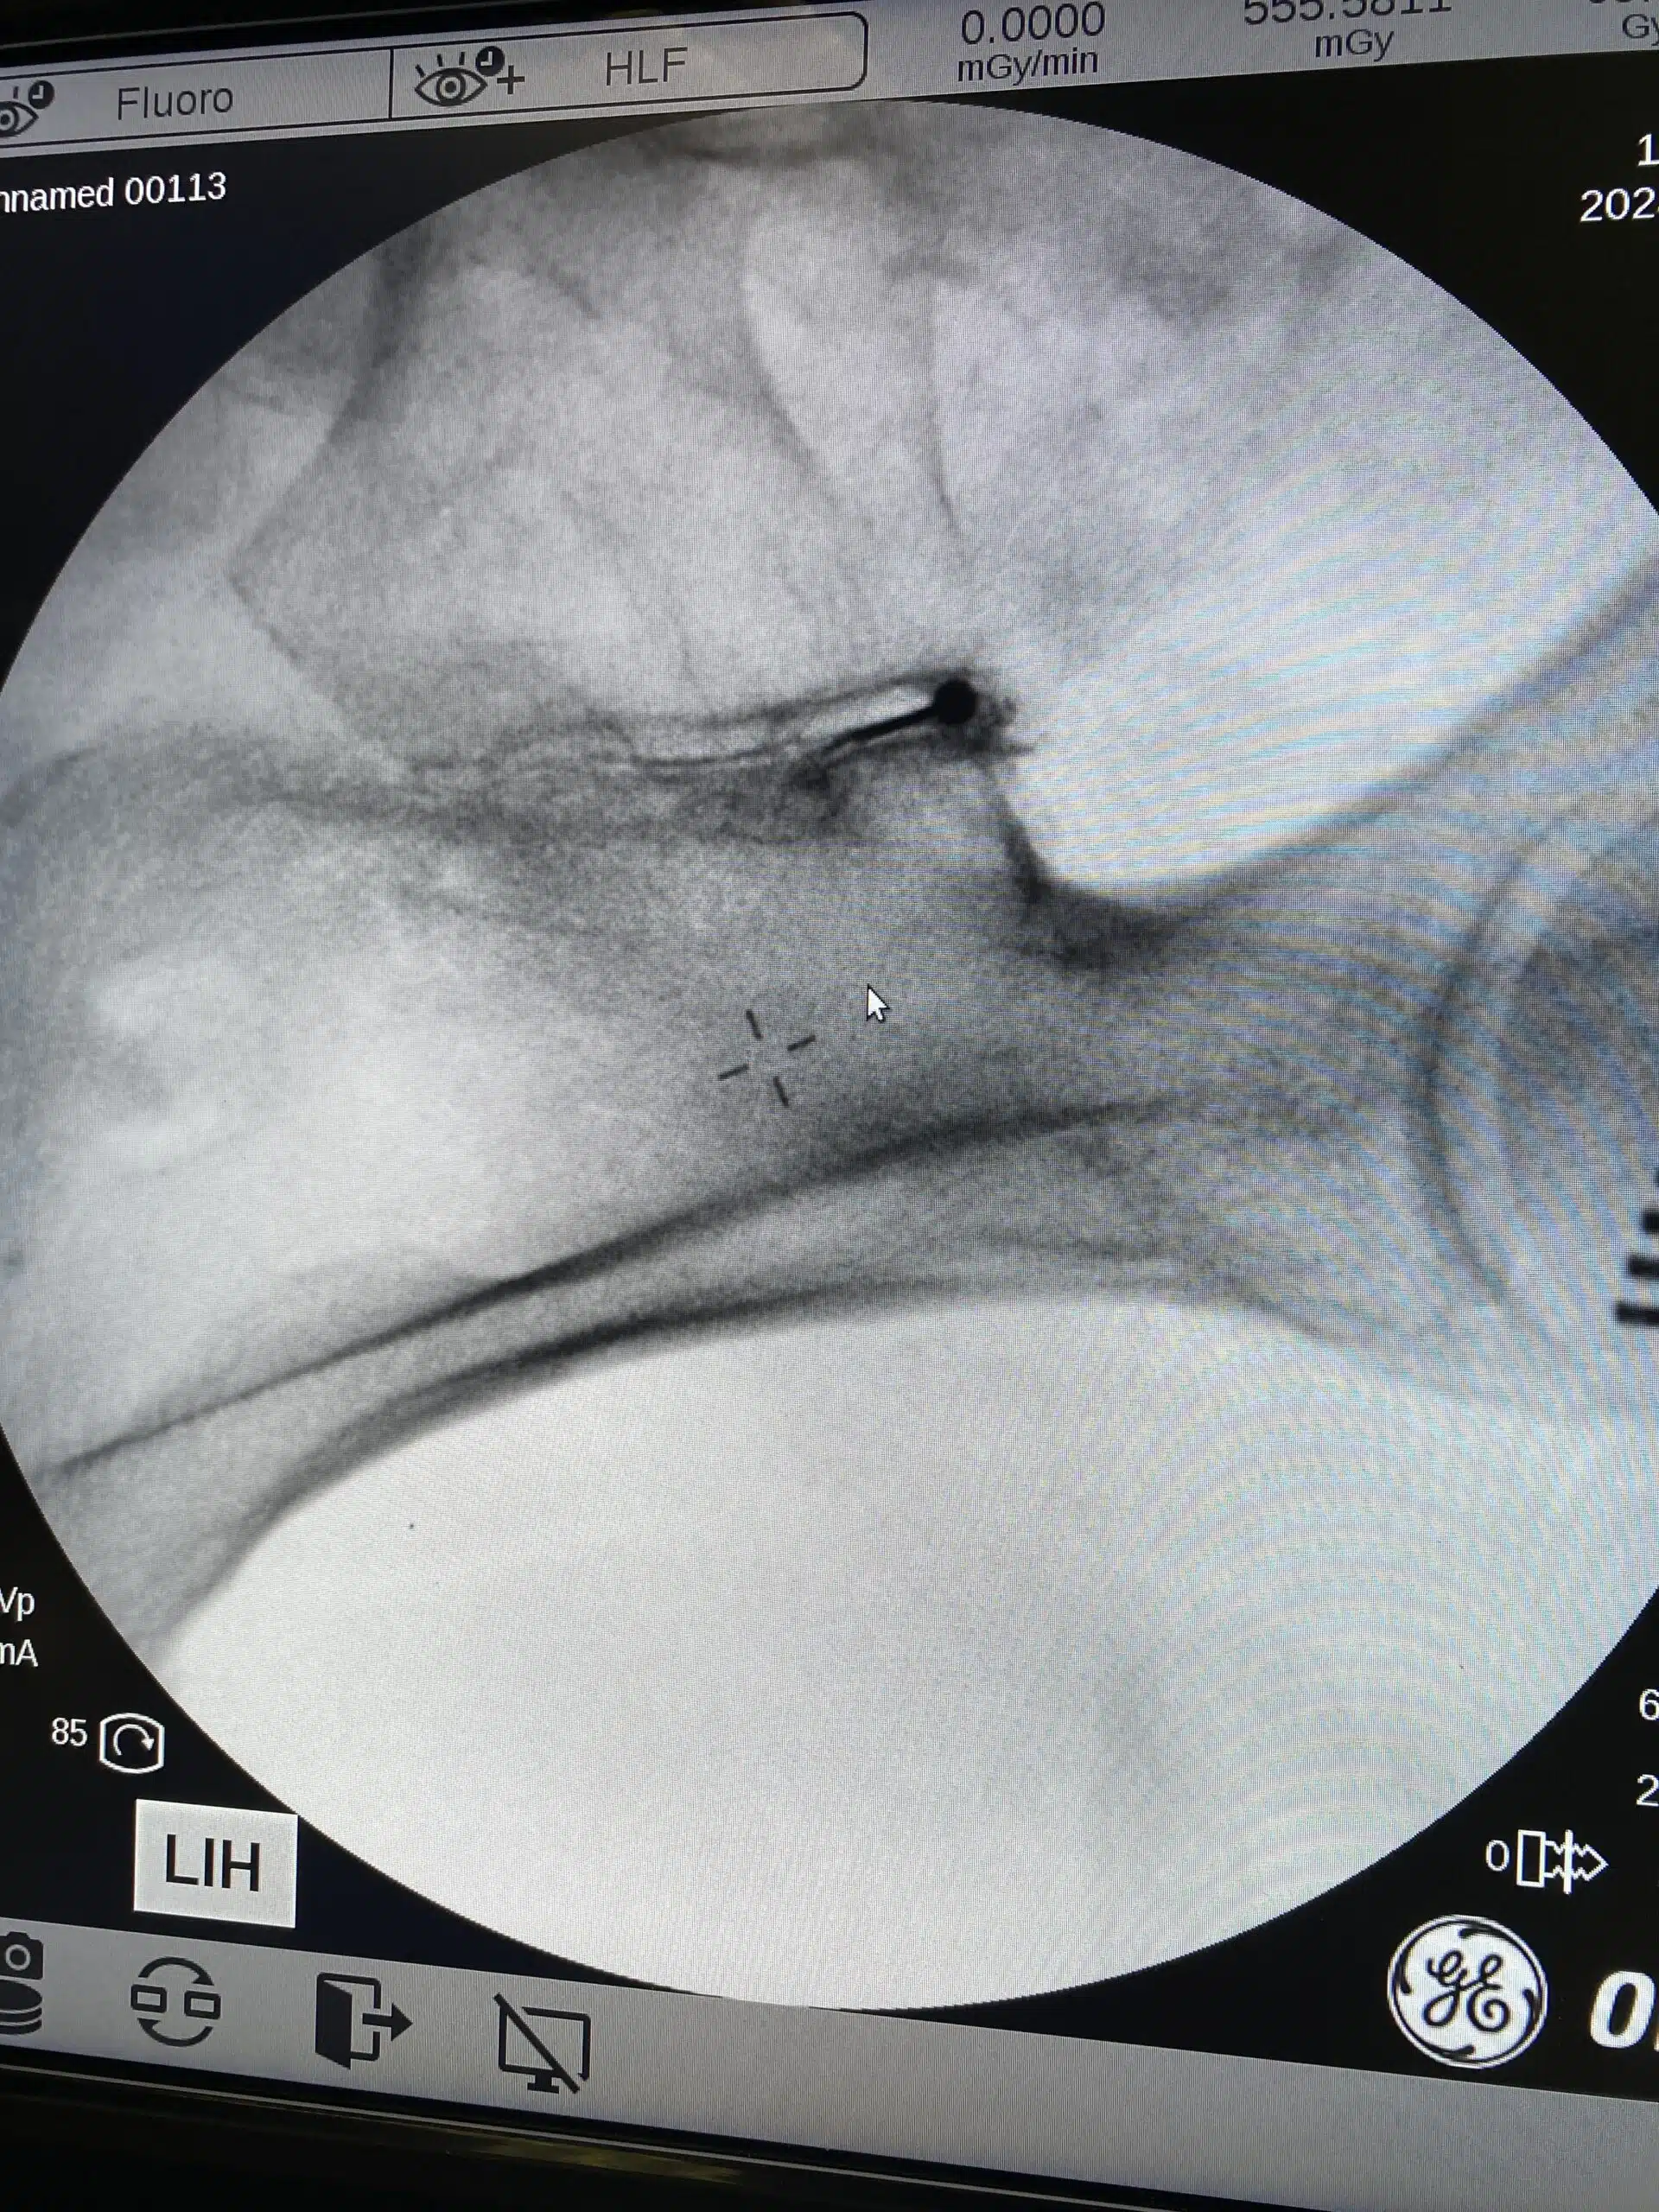

Diagnosen stilles ved kliniske tester og diagnostiske blokader. Diagnostiske blokader gjøre vi i røntgengjennomlysning. Dersom pasienten blir smertelindret av en injeksjon med lokalbedøvelse i IS-leddet har vi bekreftet diagnosen. Hvis leddet er irritert kan det være aktuelt å også legge til kortison som er et betennelsesdempende middel. Andre behandlingsalternativer er avhengig av effekt og varighet av de intraartikulære blokadene.

For å oppnå forlenget smertefrihet har vi god erfaring med å gjøre denervering med radiofrekvens av IS- leddet. Vi bruker da en spesialelektrode som kalles Simplicity. Denne plasseres på medialsiden av IS- leddet, kobles til en RF- generator som varmer opp en lengde på 6 cm langs elektroden til 80° og koagulerer nerveforsyningen inn til IS leddet. Dette kan gi flere års smertefrihet.